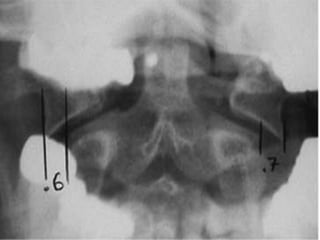

FRATURAS DO ATLAS

 A estabilidade dessas fraturas está relacionada com

a integridade do ligamento transverso

 Critério de Spence:

 Análise da radiografia transoral do paciente antes

do tratamento:

 Fratura instável : quando o afastamento das massas

laterais do atlas em relação ao áxis for maior do

que 6,9mm

 IAO: até 5 mm somente lig transvero; > 5mm tb

dos lig alates

 TC para melhor avaliação